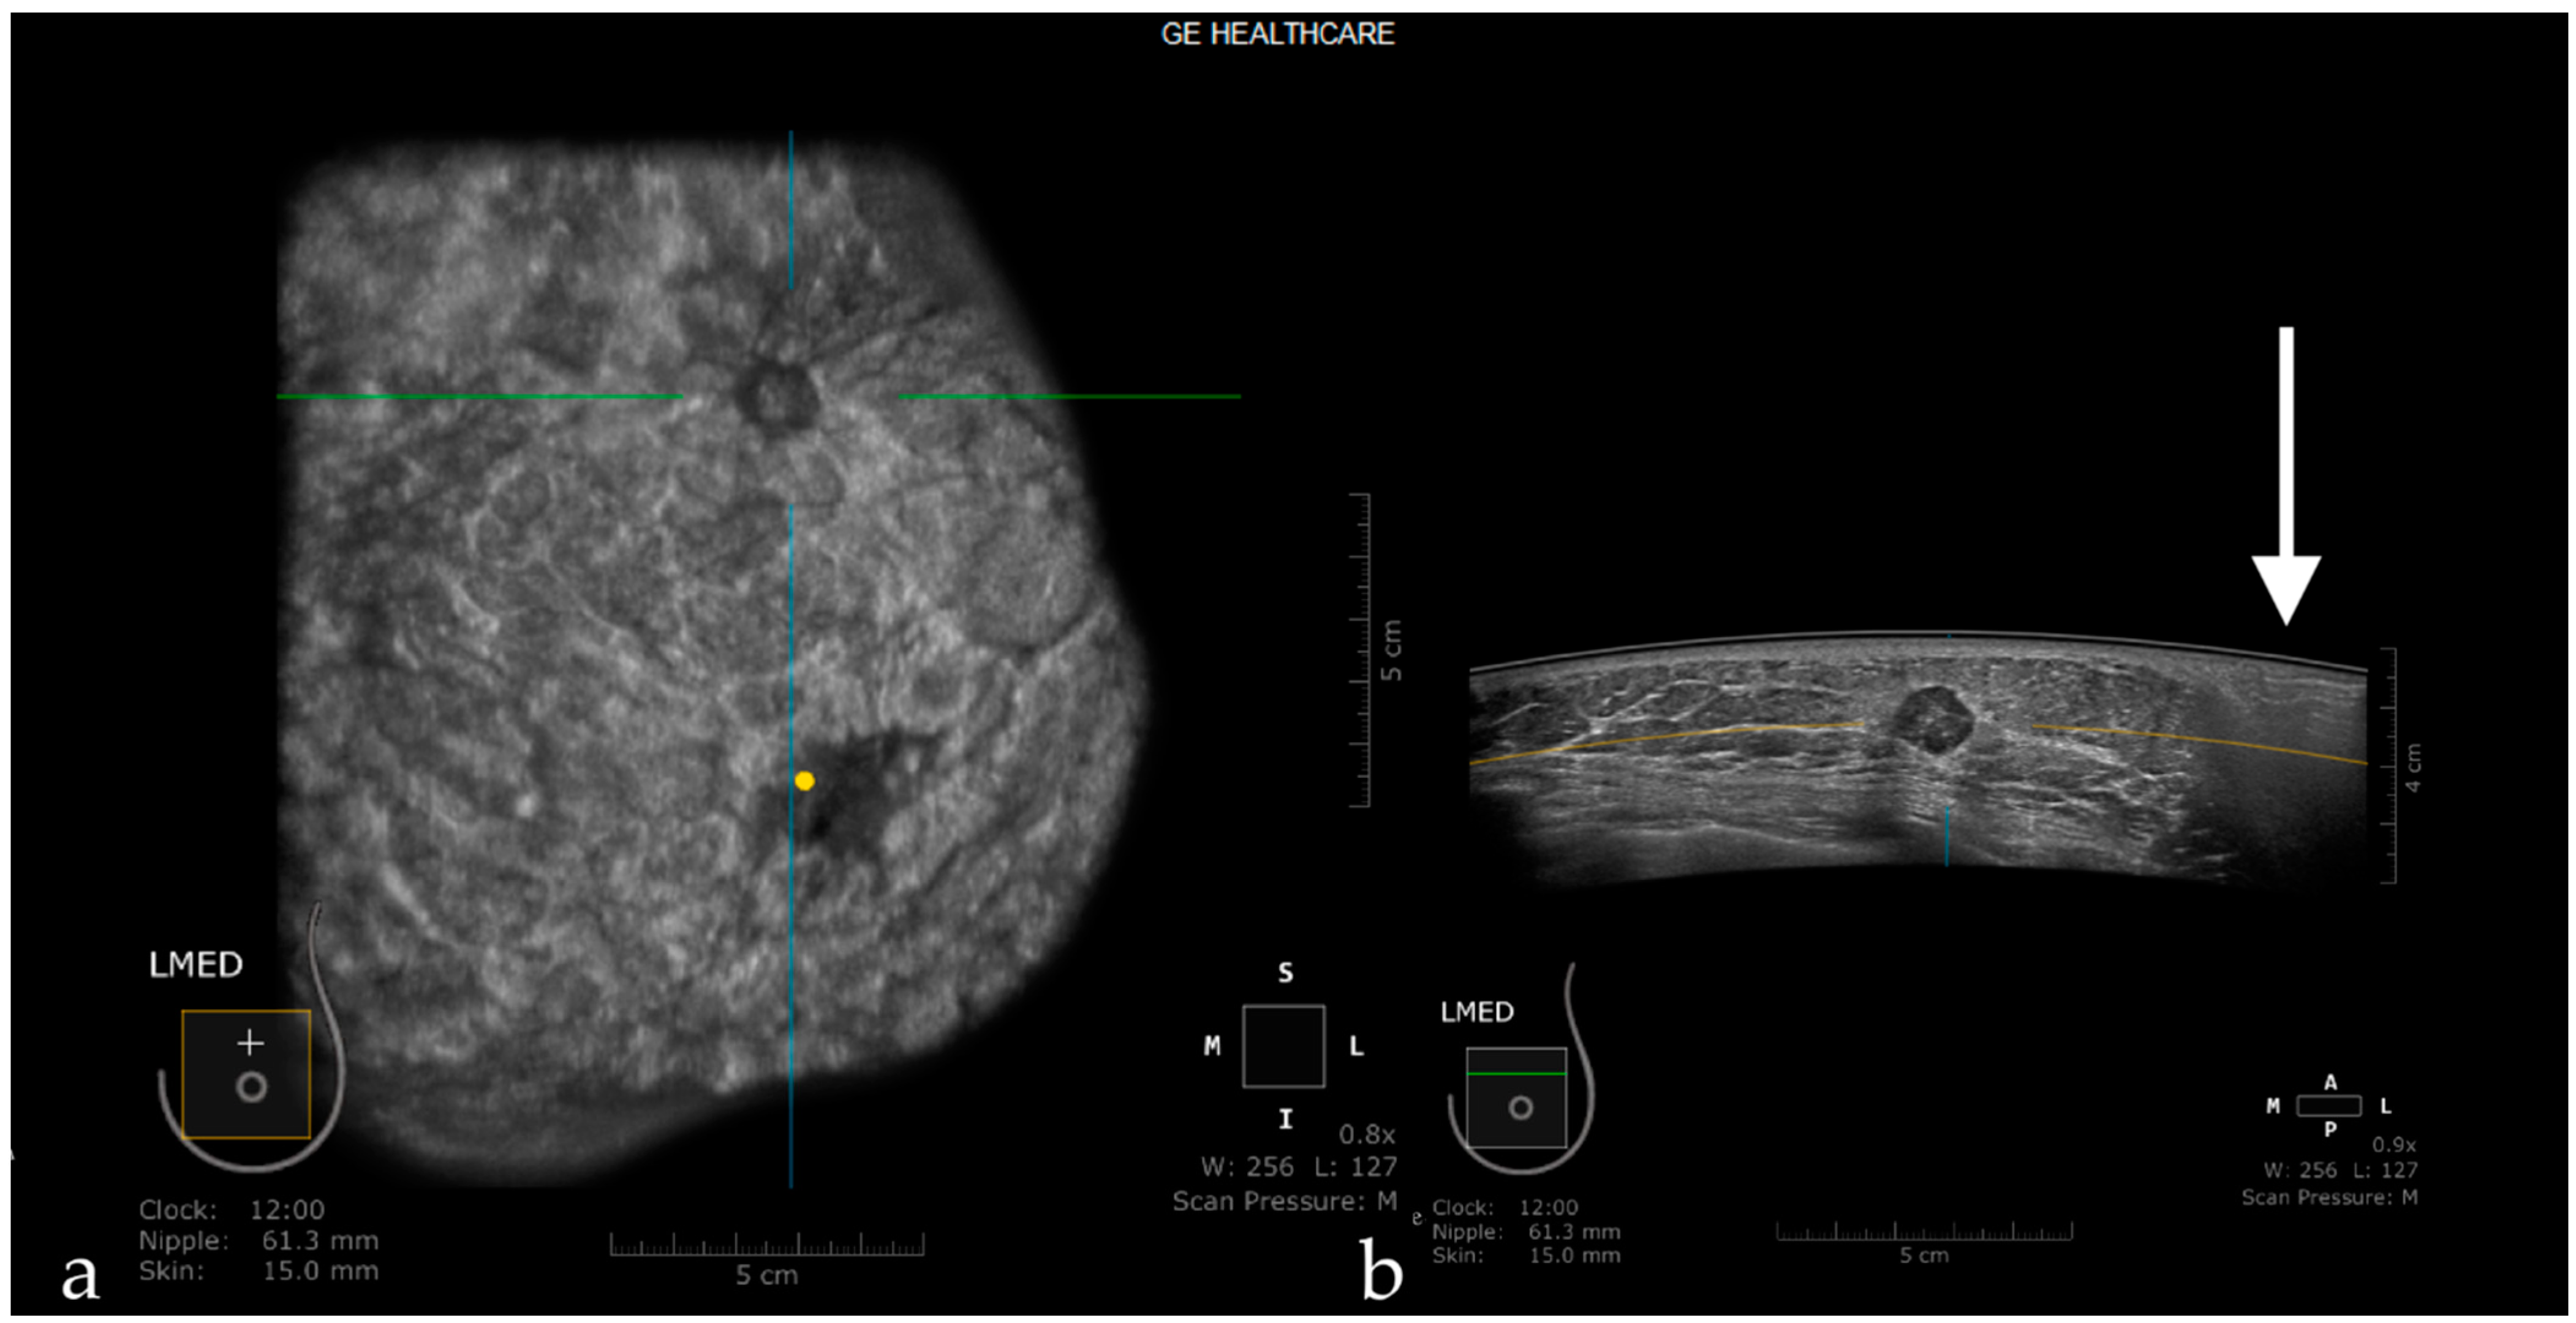

Automated screening breast ultrasound ABUS is an easy comfortable test developed specifically to help detect small cancers hidden in dense breast tissue. The scan produces 3D volumetric images viewed by a radiologist. As the transducer passes over the target area it creates a.

This test involves an automated scan of the breasts and typically takes 15 to 20 minutes to complete. Tumor classification and segmentation are two important tasks for computer-aided diagnosis CAD using 3D automated breast ultrasound ABUS images. The Automated Breast Volume Scanner ABVS by Siemens Healthcare is a standalone system that also uses a high frequency large-format transducer to acquire 3-D volumetric imaging of the breast.